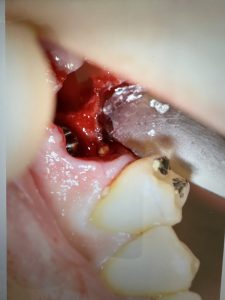

不良肉芽が凄かった方

プラットフォームスイッチングのお陰

皮質骨がシャープになっている 安定